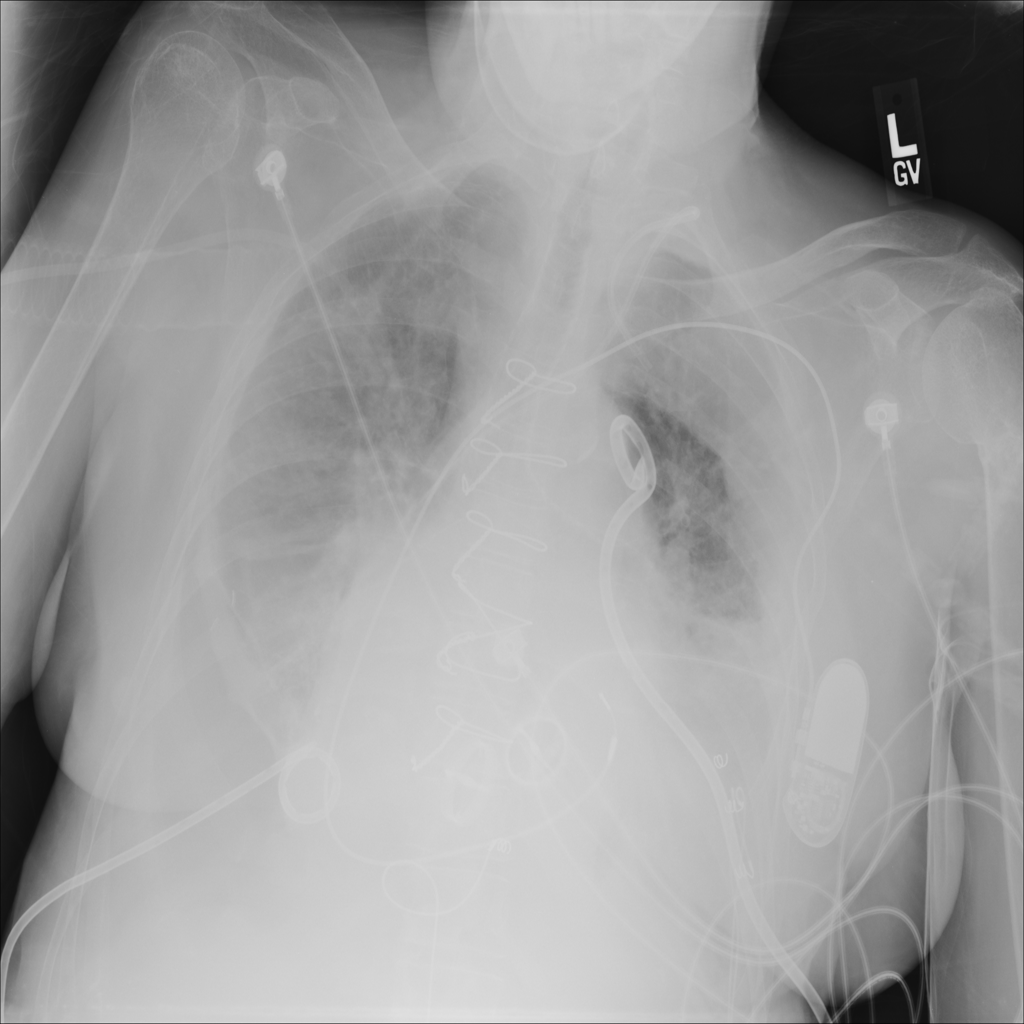

PAT-4639 · IMG-011Pneumothorax

PAT-4639 · IMG-011

AP